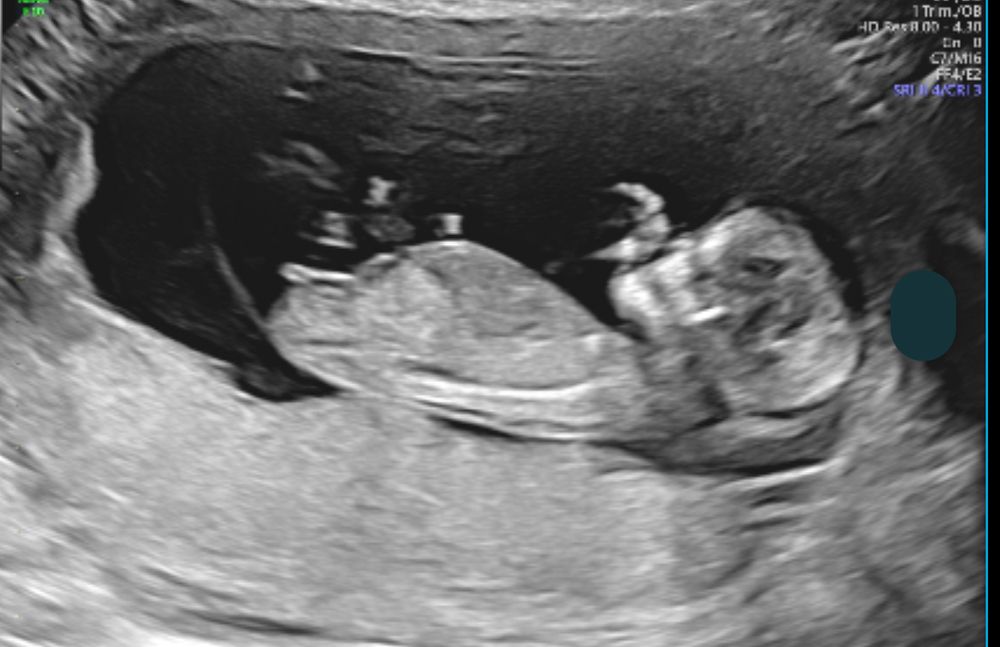

13недель кто в животике ?

На этом фото больше на девочку похоже.

Мне тоже кажется, что девочка

По наклону полового бугорка явно девочка

Ляличка пальчики сосет))))

На этом фото явно девочка)